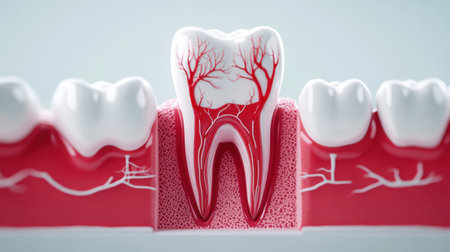

Detailed anatomical model showing human tooth structure, emphasizing root canal system. Ideal for educational purposes in dental hygiene and anatomy studies.

A close-up view of an anatomical model of a human molar tooth's cross-section. The white enamel cap transitions to yellow dentin, revealing the red pulp chamber and root canals within. The surrounding bone structure is depicted with porous texture in beige and red hues. The background is a solid, deep blue.

Detailed depiction of a tooths anatomy highlighting its internal structure and layers.

Tooth model displaying its complex internal structure including enamel, dentin, pulp, and root canals, standing against a vibrant background of colorful, out of focus lights

This image presents a detailed anatomical model of a human tooth, highlighting its layers in a contemporary dental environment for educational purposes.

Dental tooth cross section model showing enamel, dentin, pulp, gum and root structures against a soft colorful bokeh background for oral health education and dentistry study

A detailed dental model illustrates the anatomy of a human tooth highlighting its inner structure including roots and nerves. This model is used for educational purposes in a dental clinic.

This image depicts a detailed anatomical model of a human tooth, showcasing the intricate internal structures, including nerves and blood vessels, essential for educational and healthcare purposes.

Transparent tooth model displaying detailed internal anatomy, including nerves, blood vessels, and pulp structure, isolated on a gray background.